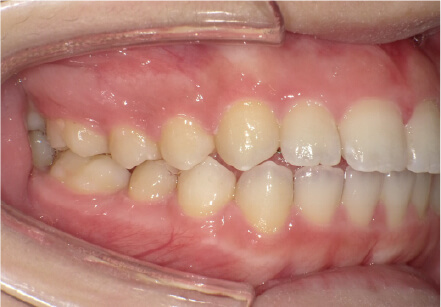

8歳

/

女性

相談内容

前歯がでている、前歯が噛み合っていない

カウンセリング・診断結果

上下叢生、顎が狭いのでクリアコレクトで拡大配列+トレーニングで進めてく

治療内容・方法

全額アライナー矯正 クリアコレクト

術後の経過・現在の様子

リンガルアーチ使用

治療のリスク

痛み・歯根吸収・歯肉退縮・虫歯・後戻り

費用・治療期間

924,000円、8ヶ月